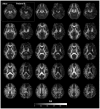

It has been proposed that self-awareness (SA), a multifaceted phenomenon central to human consciousness, depends critically on specific brain regions, namely the insular cortex, the anterior cingulate cortex (ACC), and the medial prefrontal cortex (mPFC). Such a proposal predicts that damage to these regions should disrupt or even abolish SA. We tested this prediction in a rare neurological patient with extensive bilateral brain damage encompassing the insula, ACC, mPFC, and the medial temporal lobes. In spite of severe amnesia, which partially affected his "autobiographical self", the patient's SA remained fundamentally intact. His Core SA, including basic self-recognition and sense of self-agency, was preserved. His Extended SA and Introspective SA were also largely intact, as he has a stable self-concept and intact higher-order metacognitive abilities. The results suggest that the insular cortex, ACC and mPFC are not required for most aspects of SA. Our findings are compatible with the hypothesis that SA is likely to emerge from more distributed interactions among brain networks including those in the brainstem, thalamus, and posteromedial cortices.